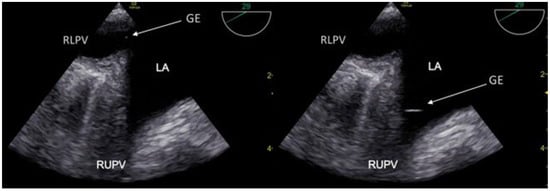

3.1. TCCD MES-Positive Case 1

3.2. TCCD MES-Positive Case 2

3.3. TCCD MES-Positive Case 3